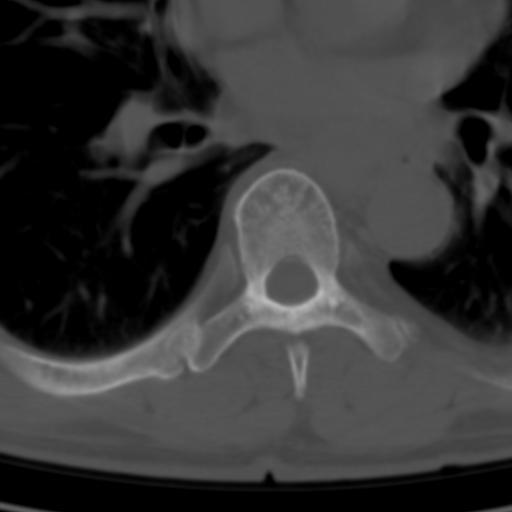

标题: CT25189:胸椎ct,请会诊!

既往食管癌,现行ct检查!

仅见椎体退行性改变

中上段食道癌,椎体轻度退变。

椎体退行性改变,食管癌。

支持中上段食道癌,椎体轻度退变,必要时做ect。

支持中上段食道癌,椎体轻度退变。